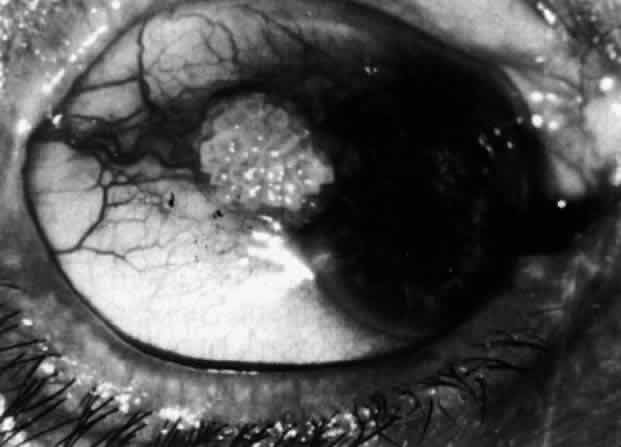

Nodular Anterior Scleritis Although patients with nodular anterior scleritis resemble those with nodular episcleritis on cursory examination, detailed examination reveals marked differences. The nodule or nodules (they may be multiple) consist of scleral tissue that is immovable episclera is tightly adherent to the nodule, which is tender to the touch. Although the sclera sometimes becomes transparent below the nodule, it does not become necrotic, nor does the condition extend beyond the site of the nodule, as occurs in necrotizing scleral disease (Fig. 36). (see Fig. 28; Figs. 34 and 35). The edematous

The angiogram is similar to that of diffuse anterior scleritis (i.e., there is a rapid filling pattern and deep scleral leakage of dye).26 Necrotizing Anterior Scleritis with Inflammation Patients with necrotizing anterior scleritis with inflammation not only suffer extremes of discomfort but are in serious danger of losing an eye. Therefore, it is of great importance that the condition be detected early and treated adequately. (It is of equal importance that those varieties of scleral inflammation that are not destructive to the eye should not be treated with drugs that are themselves dangerous.) Accurate diagnosis is the key. Necrotizing scleritis accompanied by inflammation is always painful, waking the patient at night, increasing in intensity day by day, and leading to severe distress. The sclera is swollen, and the overlying inflammation is localized to the center of a lesion or to either end of an extending lesion (Fig. 37; Color Plate 1D). After inflammation, the sclera becomes transparent so that the underlying choroidal pigment becomes visible when viewed in daylight (Fig. 38). These areas may be invisible with the slit lamp. The area of inflammation extends outward around the globe from the original site of inflammation, often joining with other areas of scleritis that have subsequently appeared. If the inflammation is not suppressed, the process will progress around the globe until the whole anterior segment is involved (Fig. 39).